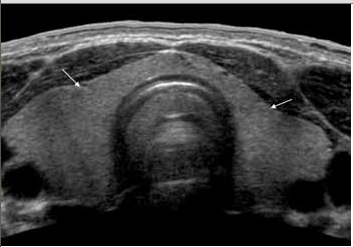

Pics from aium.org – NORMAL ADULT THYROID

normal thyroid

PAPILLARY CARCINOMAthyroid_papillary carcinoma